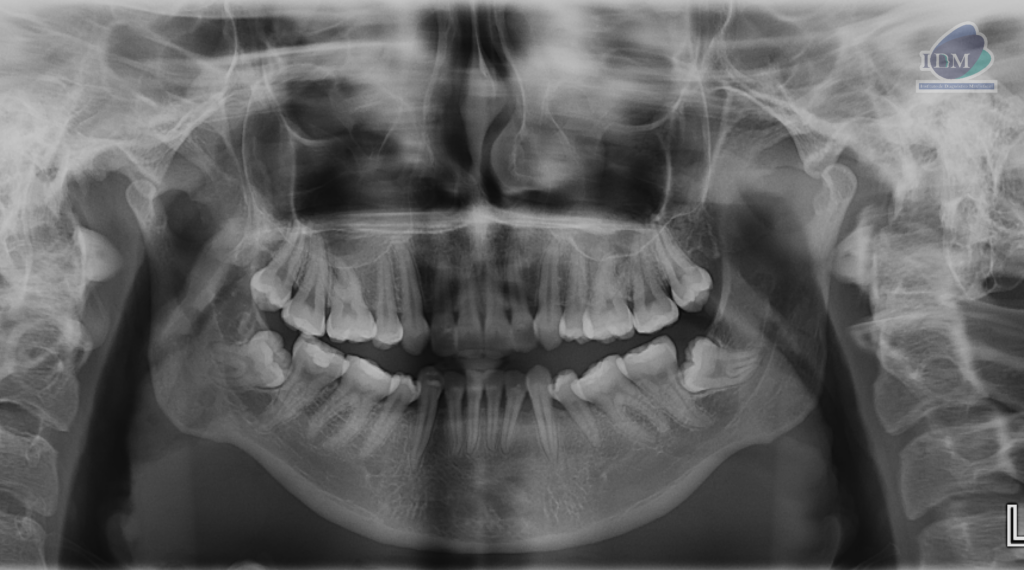

En la radiografía panorámica (Figura 1), se observa piezas 38 y 48 mesioanguladas e impactadas contra la superficie radicular distal de las piezas 37 y 47 respectivamente.

Radiografia Panorámica